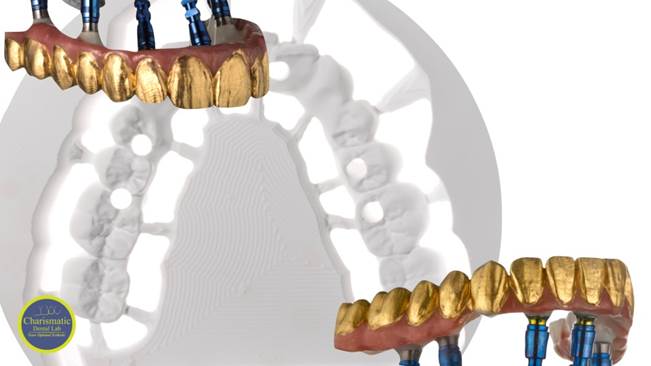

Clinical case: AFull transition from natural teeth to all-on-6 bridges

with AnyRidge implants

- Courtesy of Dr. Rabih Abi Nader, UAE -

Full-mouth rehabilitation, minimal layering, Zirconia, all-on-6, life changing result, edentulous ,Dr. Rabih Abi Nader, AnyRidge

AnyRidge implant system